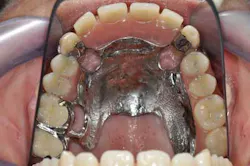

Figs. 7a, b, and c: Teeth and ceramic mounting

- Final mounting.